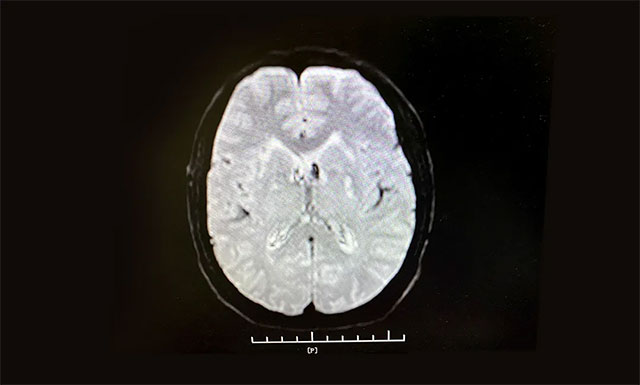

从急诊科11:11接诊,11:13建立静脉通道,到11:28影像科CT平扫排除脑出血,并告知家属,经反复沟通到11:56接受溶栓,门诊、急诊科、脑血管病科、影像科、检验科等多个科室通力合作,发挥多学科联动优势,无缝对接,DNT (Door to Needle Time——从患者入院急症科到接受溶栓治疗时间)用时为45分钟,为抢救患者的大脑功能赢得了宝贵时间。

▲ 根据急诊CT影像结果,排除患者脑出血